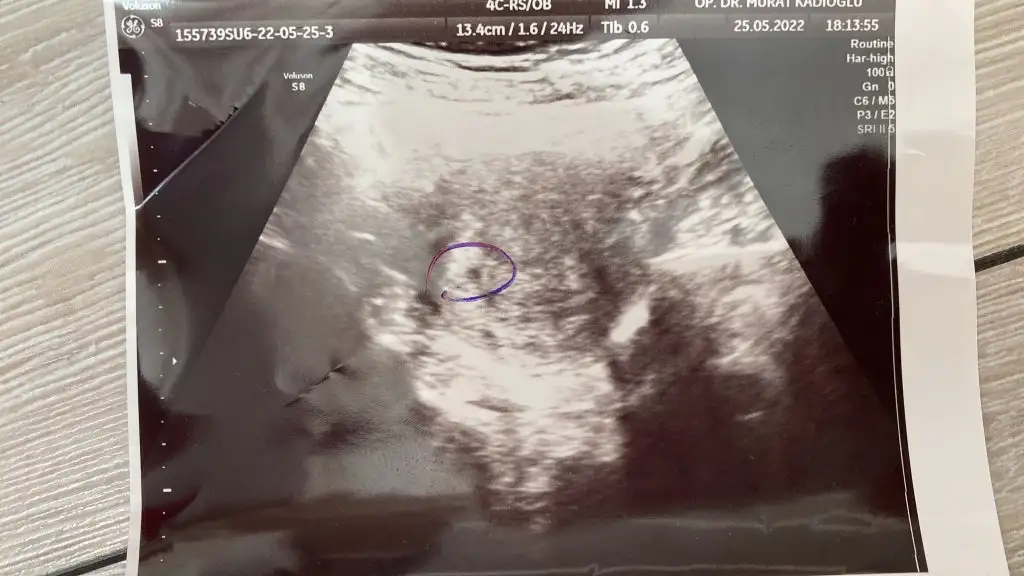

Şu an on haftalık ama 7+4'te olan ultrasonumuz bize de tahmin yapabilir misiniz bu arada karından ultrason

Çok küçük ama benim ki ne oluyor tahminlerinize göre ultrason fan bu arada